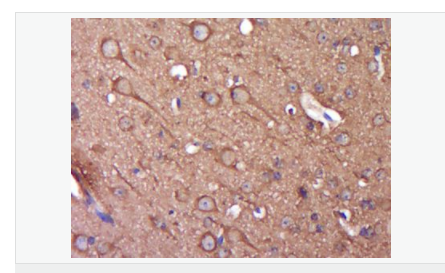

| 產品應用 | WB=1:500-2000 ELISA=1:5000-10000 IHC-P=1:100-500 IHC-F=1:100-500 Flow-Cyt=1ug/Test IF=1:100-500 (石蠟切片需做抗原修復) not yet tested in other applications. optimal dilutions/concentrations should be determined by the end user. |

| 產品介紹 | Alpha-synuclein is a member of the synuclein family, which also includes beta- and gamma-synuclein. Synucleins are abundantly expressed in the brain and alpha- and beta-synuclein inhibit phospholipase D2 selectively. SNCA may serve to integrate presynaptic signaling and membrane trafficking. Defects in SNCA have been implicated in the pathogenesis of Parkinson disease. SNCA peptides are a major component of amyloid plaques in the brains of patients with Alzheimer's disease. Alternatively spliced transcripts encoding different isoforms have been identified for this gene. [provided by RefSeq, Feb 2016].. Function: May be involved in the regulation of dopamine release and transport. Induces fibrillization of microtubule-associated protein tau. Reduces neuronal responsiveness to various apoptotic stimuli, leading to a decreased caspase-3 activation. Subunit: Soluble monomer which can form filamentous aggregates. Interacts with UCHL1. Interacts with phospholipase D and histones. Subcellular Location: Cytoplasm. Membrane. Nucleus. Cell junction, synapse. Note=Membrane-bound in dopaminergic neurons. Tissue Specificity: Expressed principally in brain but is also expressed in low concentrations in all tissues examined except in liver. Concentrated in presynaptic nerve terminals. Post-translational modifications: Note=Genetic alterations of SNCA resulting in aberrant polymerization into fibrils, are associated with several neurodegenerative diseases (synucleinopathies). SNCA fibrillar aggregates represent the major non A-beta component of Alzheimer disease amyloid plaque, and a major component of Lewy body inclusions. They are also found within Lewy body (LB)-like intraneuronal inclusions, glial inclusions and axonal spheroids in neurodegeneration with brain iron accumulation type 1. Defects in SNCA are the cause of Parkinson disease type 1 (PARK1) [MIM:168601]. A complex neurodegenerative disorder characterized by bradykinesia, resting tremor, muscular rigidity and postural instability. Additional features are characteristic postural abnormalities, dysautonomia, dystonic cramps, and dementia. The pathology of Parkinson disease involves the loss of dopaminergic neurons in the substantia nigra and the presence of Lewy bodies (intraneuronal accumulations of aggregated proteins), in surviving neurons in various areas of the brain. The disease is progressive and usually manifests after the age of 50 years, although early-onset cases (before 50 years) are known. The majority of the cases are sporadic suggesting a multifactorial etiology based on environmental and genetic factors. However, some patients present with a positive family history for the disease. Familial forms of the disease usually begin at earlier ages and are associated with atypical clinical features. Defects in SNCA are the cause of Parkinson disease type 4 (PARK4) [MIM:605543]. A complex neurodegenerative disorder with manifestations ranging from typical Parkinson disease to dementia with Lewy bodies. Clinical features include parkinsonian symptoms (tremor, rigidity, postural instability and bradykinesia), dementia, diffuse Lewy body pathology, autonomic dysfunction, hallucinations and paranoia. Defects in SNCA are the cause of dementia Lewy body (DLB) [MIM:127750]. A neurodegenerative disorder clinically characterized by mental impairment leading to dementia, parkinsonism, often with fluctuating cognitive function, visual hallucinations, falls, syncopal episodes, and sensitivity to neuroleptic medication. Brainstem or cortical intraneuronal accumulations of aggregated proteins (Lewy bodies) are the only essential pathologic features. Patients may also have hippocampal and neocortical senile plaques, sometimes in sufficient number to fulfill the diagnostic criteria for Alzheimer disease. DISEASE: Note=Genetic alterations of SNCA resulting in aberrant polymerization into fibrils, are associated with several neurodegenerative diseases (synucleinopathies). SNCA fibrillar aggregates represent the major non A-beta component of Alzheimer disease amyloid plaque, and a major component of Lewy body inclusions. They are also found within Lewy body (LB)-like intraneuronal inclusions, glial inclusions and axonal spheroids in neurodegeneration with brain iron accumulation type 1. Defects in SNCA are the cause of Parkinson disease type 1 (PARK1) [MIM:168601]. A complex neurodegenerative disorder characterized by bradykinesia, resting tremor, muscular rigidity and postural instability. Additional features are characteristic postural abnormalities, dysautonomia, dystonic cramps, and dementia. The pathology of Parkinson disease involves the loss of dopaminergic neurons in the substantia nigra and the presence of Lewy bodies (intraneuronal accumulations of aggregated proteins), in surviving neurons in various areas of the brain. The disease is progressive and usually manifests after the age of 50 years, although early-onset cases (before 50 years) are known. The majority of the cases are sporadic suggesting a multifactorial etiology based on environmental and genetic factors. However, some patients present with a positive family history for the disease. Familial forms of the disease usually begin at earlier ages and are associated with atypical clinical features. Defects in SNCA are the cause of Parkinson disease type 4 (PARK4) [MIM:605543]. A complex neurodegenerative disorder with manifestations ranging from typical Parkinson disease to dementia with Lewy bodies. Clinical features include parkinsonian symptoms (tremor, rigidity, postural instability and bradykinesia), dementia, diffuse Lewy body pathology, autonomic dysfunction, hallucinations and paranoia. Defects in SNCA are the cause of dementia Lewy body (DLB) [MIM:127750]. A neurodegenerative disorder clinically characterized by mental impairment leading to dementia, parkinsonism, often with fluctuating cognitive function, visual hallucinations, falls, syncopal episodes, and sensitivity to neuroleptic medication. Brainstem or cortical intraneuronal accumulations of aggregated proteins (Lewy bodies) are the only essential pathologic features. Patients may also have hippocampal and neocortical senile plaques, sometimes in sufficient number to fulfill the diagnostic criteria for Alzheimer disease. Similarity: Belongs to the synuclein family. SWISS: P37840 Gene ID: 6622 Database links: Entrez Gene: 6622 Human Entrez Gene: 20617 Mouse Omim: 163890 Human SwissProt: P37840 Human SwissProt: O55042 Mouse Unigene: 21374 Human Unigene: 17484 Mouse Unigene: 1827 Rat Important Note: This product as supplied is intended for research use only, not for use in human, therapeutic or diagnostic applications. Synuclein 包括α-Synuclein,β-Synuclein 和γ-Synuclein 是神經細胞中富含的前突觸蛋白。α-Synuclein,Alzheimer’(AD)病淀粉樣蛋白沉積的成份之一,集中分布在神經細胞的包體和突觸。在帕金森病人中發現有α-Synuclein的變異型,而γ-Synuclein與軸突病理學有關。此抗體將為Lewy小體癡呆癥、Parkinson癥、AD和其它一些神經性疾病提供有用的病理診斷。 |